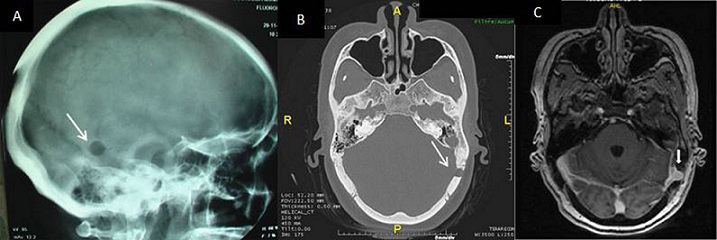

Lacune de la voûte du crâne révélatrice d’un sinus pericranii

Les lacunes de la voûte du crâne sont observées sur environ 40% des radiographies standard du crâne. Elles sont découvertes le plus souvent de façon fortuite lors d'un bilan radiologique pour sinusite ou traumatisme crânien ou de façon systématique, au cours du bilan d'extension d'hémopathies ou de cancers ostéophiles. Elles sont exceptionnellement révélatrices d'un sinus pericranii. Il s'agit d'une anomalie vasculaire rare réalisant un drainage veineux entre les systèmes extra- et intracrâniens. Le diagnostic repose sur le scanner et/ou l'IRM, qui visualisent une importante prise de contraste de la lésion. Le traitement chirurgical est assez lourd et rarement indiqué. Nous rapportons l'observation d'une patiente âgée de 53 ans, aux antécédents de carcinome basocellulaire du nez, adressée pour bilan étiologique d'une lacune du crane. Le bilan biologique (numération formule sanguine, vitesse de sédimentation, protéine C-réactive, calcémie, électrophorèse des protéines) était normal. La tomodensitométrie du massif facial objectivait une image lacunaire de 9 mm à l'emporte pièce de l'os temporal gauche. A l'imagerie par résonance magnétique, la lacune est en regard du sinus transverse gauche avec lequel elle se continue et se rehausse de la même façon que le sinus après injection de gadolinium. Le diagnostic de sinus pericranii a été retenu. Devant l'absence de plainte fonctionnelle une simple surveillance a été décidée.